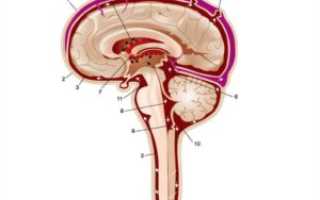

В местах, где субарахноидальное пространство естественным образом расширено, образуются мозговые цистерны, это значит, что основной объем циркулирующей цереброспинальной жидкости содержится в этих полостях. Подпаутинные цистерны – зоны естественного увеличения объема субарахноидального пространства, которые преимущественно находятся у основания мозга головы. Самые большие цистерны – базальная и затылочная.

Неравномерное расширение области субарахноидального пространства, расположенного в головном мозге, у взрослых пациентов встречается редко. Чаще патология выявляется у детей младенческого возраста. У новорожденных объем подпаутинной полости в норме меньше, чем у взрослого. Мозговые цистерны представляют собой часть сети, по которой осуществляется циркуляция цереброспинальной жидкости.

Цистерны – внешние резервуары, в то время как желудочки – внутренние. Если процессы продукции и резорбции (всасывание) ликвора уравновешивают друг друга, циркуляция поддерживается в нормальном режиме.

Головной мозг человека окружают три защитные оболочки – твердая, паутинная и мягкая. Последняя непосредственно прилегает к мозговому веществу и обеспечивает его питание. Паутинная оболочка соединена с другими оболочками мозга с помощью соединительнотканных перепонок. В областях, где перепонки отсутствуют, находятся цистерны.

Спинномозговая жидкость циркулирует в 4-х желудочках мозга (третьем, четвертом и двух боковых) и субарахноидальном пространстве. Ликвор выполняет функции питания нейронов, выведения продуктов обмена веществ, механической защиты мозга.